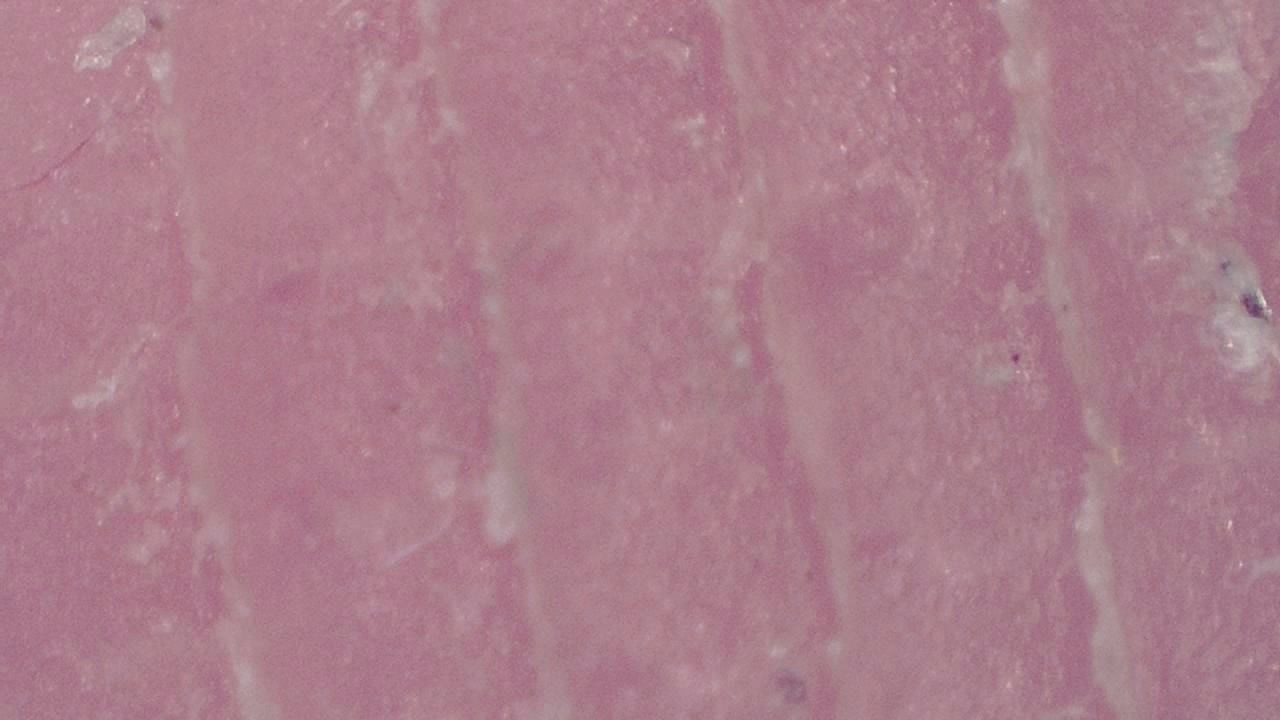

With variable magnification, it is possible to examine everything from superficial structures to deeper epidermal layers, identifying pigmentation patterns, abnormal vascularization, and textural changes that may go unnoticed to the naked eye.

- Visualization of dermal structures with up to 250× magnification

Contact dermatitis assessment

In an allergy clinic, the specialist uses the microscope to analyze the texture and vascularity of eczema-affected areas, documenting treatment response over time and adjusting therapy based on visual findings.